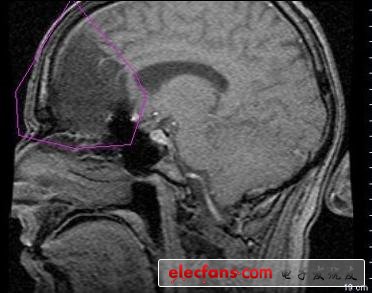

Ultrabeam是首個(gè)伽馬射線激光。美國(guó)軍方熱衷于Ultrabeam是因?yàn)閄射線可以用于對(duì)感興趣的材料進(jìn)行檢測(cè),像對(duì)進(jìn)口的集成箱,和入境人員進(jìn)行檢測(cè)等等。在醫(yī)學(xué)領(lǐng)域,它的潛力巨大。簡(jiǎn)潔的伽馬射線激光器可以使新型的放射療法和診斷工具得以應(yīng)用。